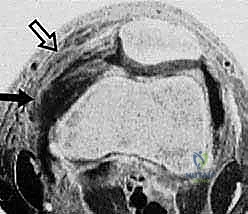

FIG 2E. Transverse gradient-echo image of the knee obtained at the level of the insertion of the adductor magnus tendon 3 weeks after lateral patellar dislocation demonstrates a complete tear of the femoral origin of the MPFL, with MPFL fibers retracted anteriorly ( solid arrow ). Partial injury, with surrounding edema, to the midsubstance of the patellar retinaculum ( open arrow ) also is seen.

<figure class="operative-step-slider my-4 text-center p-3 border rounded shadow-sm bg-light">

FIG 2F. Transverse gradient-echo image of the knee in a different patient 2 days after lateral patellar dislocation showing partial injury to the femoral origin of the MPFL. The MPFL fibers ( solid white arrow ) are wavy and show longitudinal split, and there is extensive surrounding edema. A complete tear ( open arrow ) is seen in the patellar insertion of the medial patellar retinaculum. A large joint effusion with layering ( black arrows ) is present, consistent with hemarthrosis. Note also the inferior fibers of the VMO ( arrowheads ).